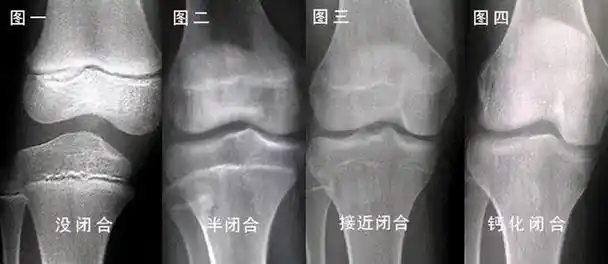

总的来说,只要孩子骨骺没有闭合,都有长高的机会.

骨骺一旦闭合,也就是要结束生长了.